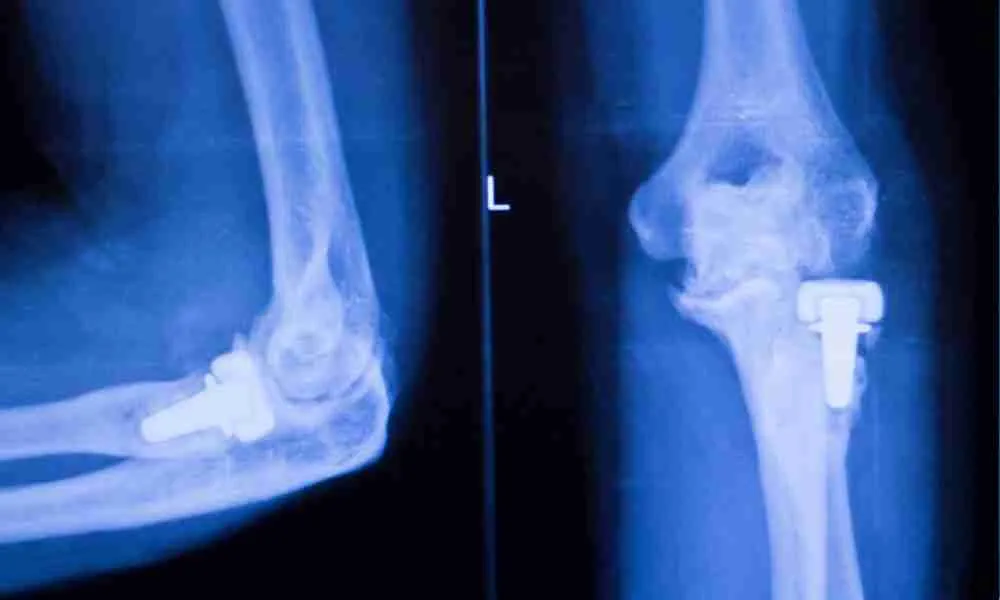

Joint replacements, such as knee, hip, and shoulder implants, have significantly enhanced the lives of individuals suffering from chronic pain and mobility limitations. However, despite their success, recalls do occur. These recalls can be concerning for patients, as they may have implications for both health and well-being. This blog will explain what a recalled joint implant means, why these implants are recalled, how patients are notified, and the steps to take if you find yourself with a recalled implant.

Joint implants are designed to alleviate pain and improve mobility for patients with joint-related conditions. However, recalls occur for various reasons, primarily concerning issues with the implant’s design, materials, or performance. Some of the common reasons for joint implant recalls include:

Design or Manufacturing Defects

A design or manufacturing process flaw can affect the implant’s function. For instance, the failure of dual-modular hip implants was attributed to issues like fretting and corrosion between components, leading to a recall (Elmallah et al., 2016).